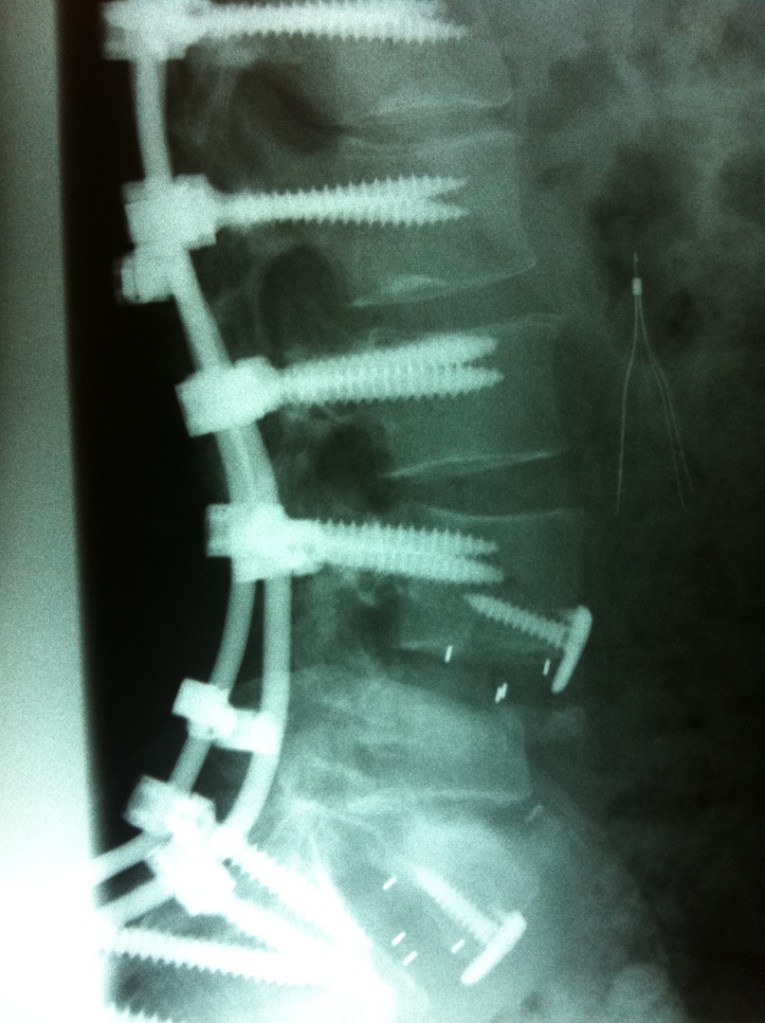

GET BUSY LIVING is an inspiring new documentary following one thrill-seeking couple’s unique love story. He survived a crippling skydiving accident. She supported him through a painful recovery. Together they aspired to jump out of a plane again.